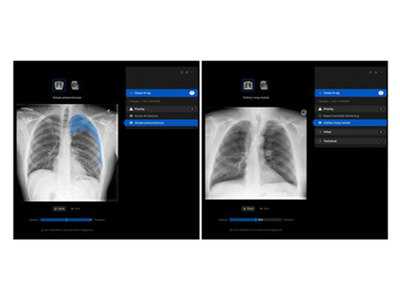

Bangalore (Karnataka) [India], January 28: Manipal Hospitals, one of India's foremost integrated healthcare providers, has adopted a leading Australian decision-support solution for their radiology practice. Harrison.ai's chest X-ray (CXR) and Reporting solutions are being used to improve the efficiency, quality, and turnaround time of chest X-ray reporting, which is one of the preliminary and most widely used imaging tests across the globe.

The solution is deployed within the radiology department, where it will assist radiologists by triaging studies, identifying and localising findings, and generating AI-assisted draft reports. These draft reports are reviewed and validated by radiologists prior to sign-off, ensuring full clinical oversight and control.

"We are proud to partner with Manipal Hospitals on the deployment of Harrison's CXR solution in India," said Dr Aengus Tran, CEO of Harrison.ai. "The solution which can detect and localise close to 125 findings helps clinicians ensure accuracy of diagnosis. This collaboration reflects a shared vision to responsibly apply AI in healthcare, supporting clinicians, improving efficiency, and ultimately enhancing patient care and experience."